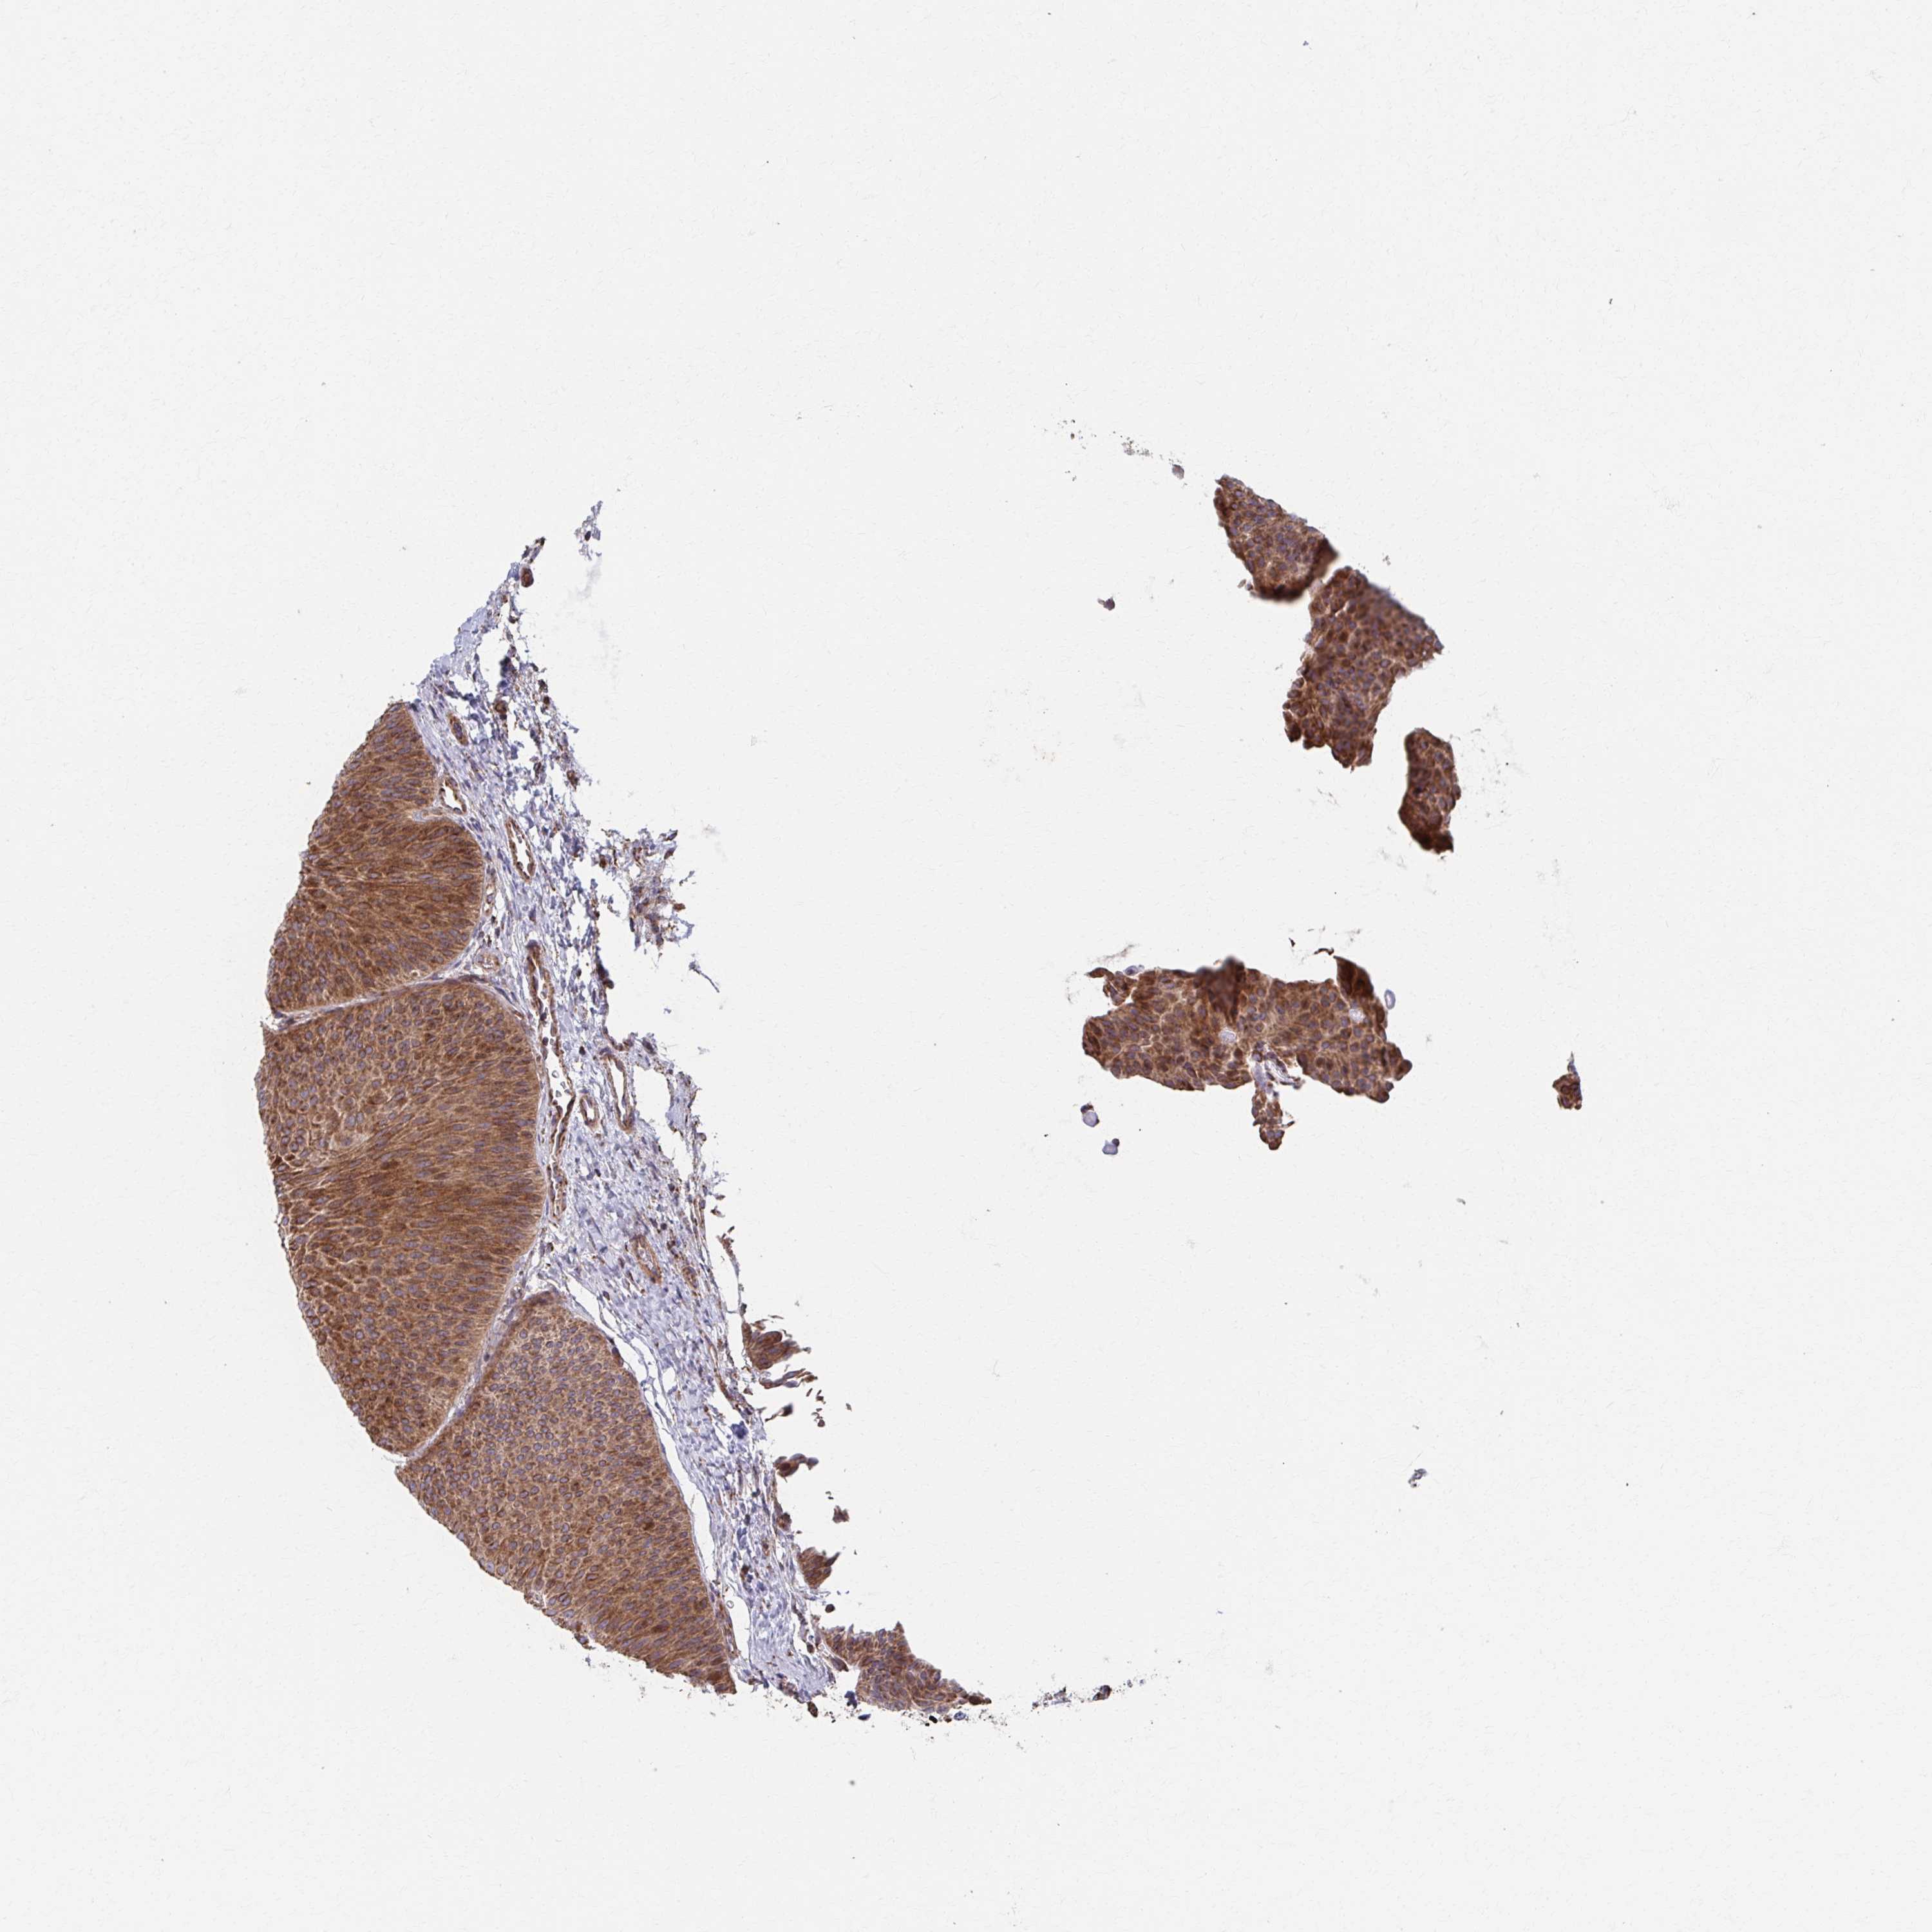

UROTHELIAL CANCER - Protein expressioni

A mouse-over function shows sample information and annotation data. Click on an image to view it in a full screen mode. Samples can be filtered based on level of antibody staining by selecting one or several of the following categories: high, medium, low and not detected. The assay and annotation is described here.

Note that samples used for immunohistochemistry by the Human Protein Atlas do not correspond to samples in the TCGA dataset.

Antibody stainingi

Antibody staining in the annotated cell types in the current human tissue is reported as not detected, low, medium, or high, based on conventional immunohistochemistry profiling in selected tissues. This score is based on the combination of the staining intensity and fraction of stained cells.

Each image is clickable and will lead to virtual microscopy that enables deeper exploration of all samples and also displays staining intensity scores, fraction scores and subcellular localization as well as patient and tissue information for each sample.

Antibody HPA055312

Antibody CAB047343

Antibody CAB069914

Staining

High

Medium

Low

Not detected

Intensity

Strong

Moderate

Weak

Negative

Quantity

>75%

75%-25%

<25%

None

Location

Nuclear

Cytoplasmic/membranous

Cytoplasmic/membranous,nuclear

Urothelial carcinoma, High grade

Urothelial carcinoma, Low grade

Urothelial carcinoma, NOS